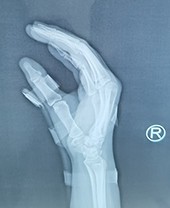

指骨骨折闭合穿针固定

小夹板治疗指骨骨折一例